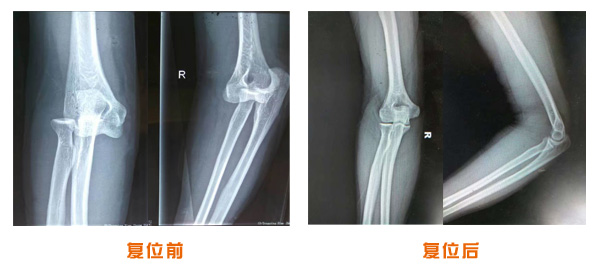

肥城市安駕莊梁氏骨科醫(yī)院是一所以梁氏手法正骨配合膏藥為特色的現(xiàn)代化專(zhuān)科醫(yī)院。

梁氏骨科術(shù)始創(chuàng)于清雍正年間,歷經(jīng)八代,至今已有三百年歷史。據(jù)1929年泰安縣志載“梁瑞圖先生,字增生,號(hào)蓮峰,安駕莊人,精岐黃并發(fā)明接骨,凡跌打車(chē)凡跌打車(chē)軋皮不破而碎骨者......【詳細(xì)】 |